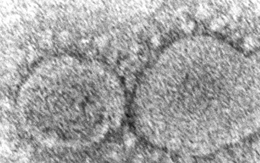

Các nhà khoa học Trung Quốc tìm thấy tỉ lệ cao các mẫu môi trường dương tính với SARS-CoV-2 ở khu bán nhiều động vật hoang dã của ngôi chợ ở Vũ Hán, cho thấy khả năng virus tồn tại ở nhiều người và động vật chứ không chỉ liên quan đến con lửng chó.

Một nghiên cứu mới cho thấy, gấu mèo có liên quan đến nguồn gốc của COVID-19 và đại dịch có thể bắt nguồn từ động vật chứ không phải do rò rỉ từ phòng thí nghiệm.

Phân tích dữ liệu di truyền từ các mẫu dương tính với SARS-CoV-2 tại chợ hải sản ở Vũ Hán, một nhóm nghiên cứu quốc tế đã tìm ra manh mối liên kết nguồn gốc đại dịch với những con gấu mèo.